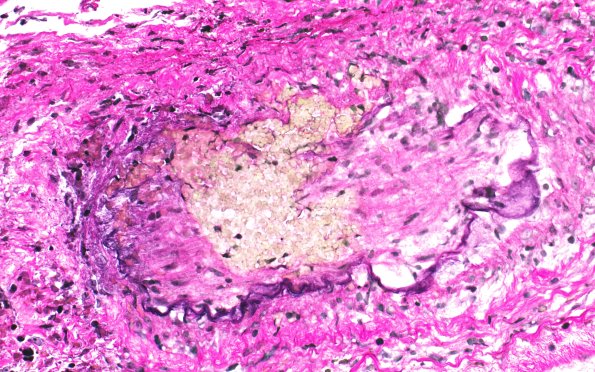

Two magnifications of the same small arteriole showing disruption of the internal elastic lamina (arrow, 7C2). (Elastin)